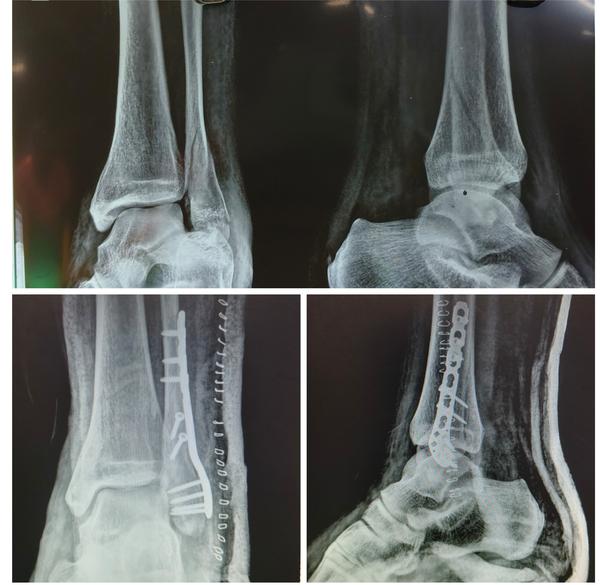

Young male had a fall while working, sustained inj...